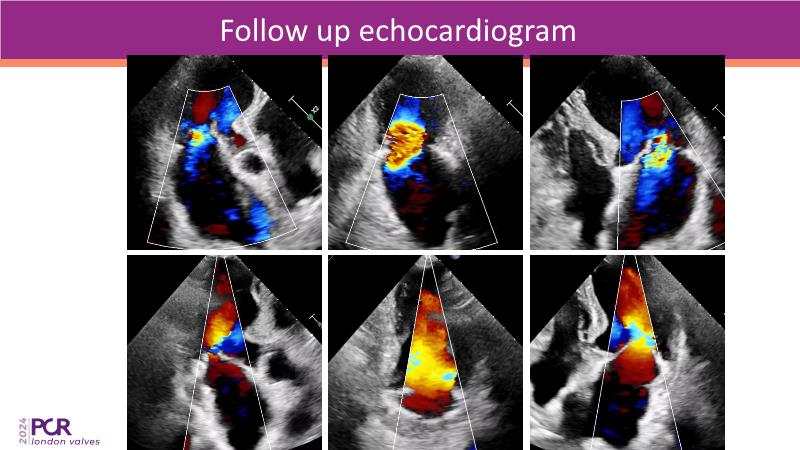

This session on mitral regurgitation offers an in-depth look at the EMPOWER trial outcomes, indirect annuloplasty in aFMR, and remodeling with the CARILLON device. Explore the benefits of early treatment for secondary mitral regurgitation, understand the role of left ventricular reverse remodeling, and review the latest clinical evidence supporting indirect annuloplasty. Discover how this technique keeps future treatment options open while expanding therapeutic possibilities for aFMR.

- To understand the importance of early treatment of secondary mitral regurgitation and the clinical benefits associated with left ventricular reverse remodeling